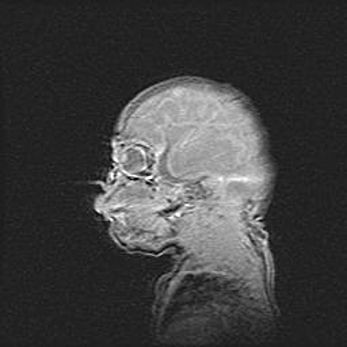

Лейкомаляция с кистозно-глиозной дегенерацией головного мозга.

Возраст: 2 месяца 25 дней

Вес: 6400 г

Окружность головы: 40 см

Срок гестации: 41 неделя

Лейкомаляцию относят к ишемически-гипоксическим повреждениям головного мозга, диагностируемым у новорожденных. При лейкомаляции в головном мозге обнаруживают очаги некроза, возникшие после тяжелой гипоксии и нарушения кровотока. В процессе морфогенеза очаги проходят три стадии: 1) развития некроза, 2) резорбции и 3) формирования глиозного рубца или кисты. Перивентрикулярная лейкомаляция (ПЛ) встречается примерно в 12% случаев среди новорожденных, обычно – у недоношенных детей, причем, частота ее зависит от массы, с которой младенец появился на свет. Наибольшее число малышей страдает лейкомаляцией, если масса при рождении 1500-2500 г.